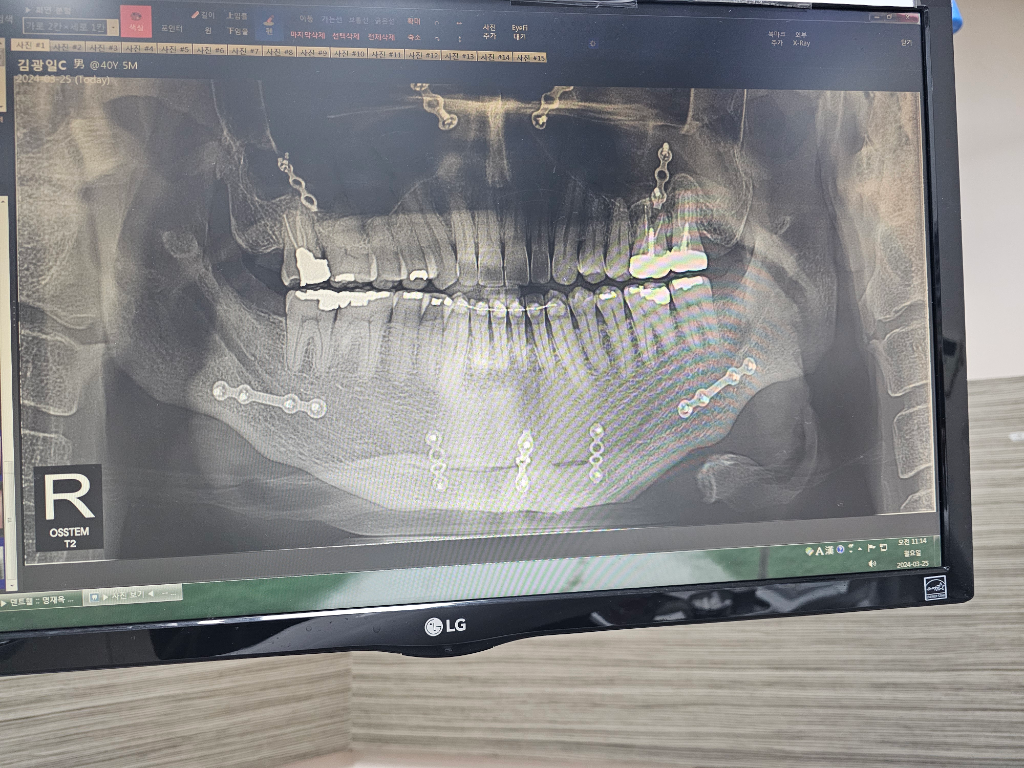

치아 사진상 으로 안뽑고 염증치료 가능한가요?

동네의원 갔더니 발치하고 치료해야 할 것 같다네요

사진상으로 안보이지만 윗니 오른쪽에서 두번째 잇몸에 물혹이 있습니다

염증때메 그렇다는데..

치아뿌리 쪽에 염증이 있는 것으로 보입니다. 또한 치아 내부에 기둥이 들어가 있어서 제 신경치료에 난이도가 높아 보이기도 합니다. 해당 지하에 뿌리 쪽에 염증이 보이는데 불편하지 않으면 사용하시는 것이 좋으며 불편감이 크다면 발치를 해야 할 가능성이 높습니다. 자세한 확인을 위해서 치과에서 진료를 받아보세요.

치아 뿌리끝으로 검게 염증 잡힌 것이 보이긴 합니다. 다만, 이전에 신경치료가 되었던 치아로 전/후 비교 사진이 있으면 더 판단에 도움이 되고, 치근단 방사선사진(작은 사진)이 해상도가 더 좋으므로 판단에 도움이 됩니다.

검게 보이는 부분은 염증으로 인해 뼈가 녹은 것입니다. 이대로 두면 더 뼈가 녹을 수도 있어 좋지 않고 발치 또는 재신경치료, 치근단 절제술 등 어떤 처치를 해줘야 합니다.